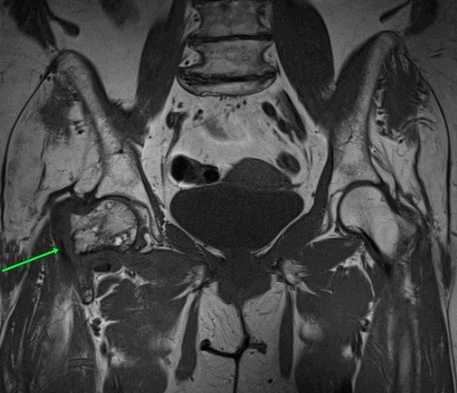

МРТ тазобедренных суставов.

МР-признаки базисцервикального перелома шейки правой бедренной кости с наличием зон инфаркта головки и шейки правой бедренной кости, синовита правого тазобедренного сустава, отека окружающих мягких тканей справа.

Перед операцией по поводу лечения перелома шейки бедра, вертлужной впадины, делают МРТ.